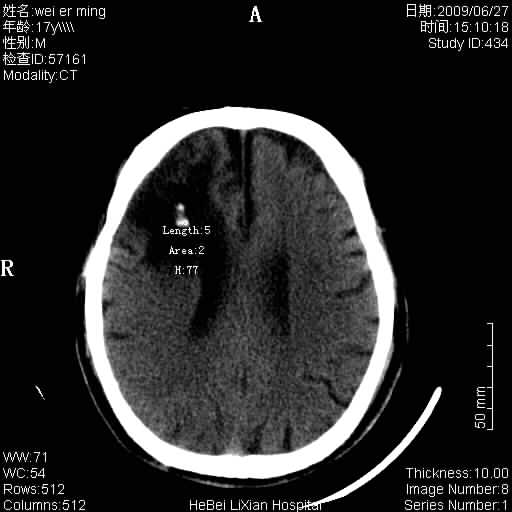

标题: CT20838:帮忙看看,是软化灶吗?

患者,男,67岁.既往有脑血栓病史.若是软化灶里面怎么出现钙化呢?

脑软化灶伴灶内钙化,钙化可能是梗塞后出血,出血钙化.

是脑软化灶,其内的钙化可解释为闭塞血管内的血栓钙化。

脑梗塞后形成的软化灶内可以有钙化密度影,系血管出血机化或血管内血栓钙化所致。